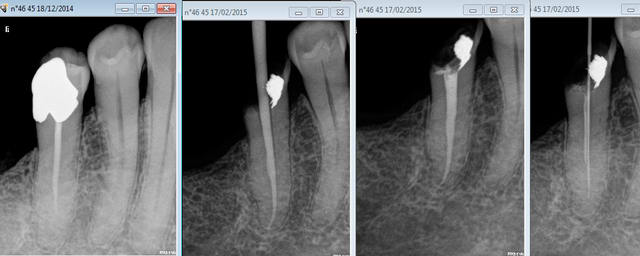

Capture d e cran 2015 02 17 19.37 - Eugenol

Capture d e cran 2015 02 19 17.45 - Eugenol